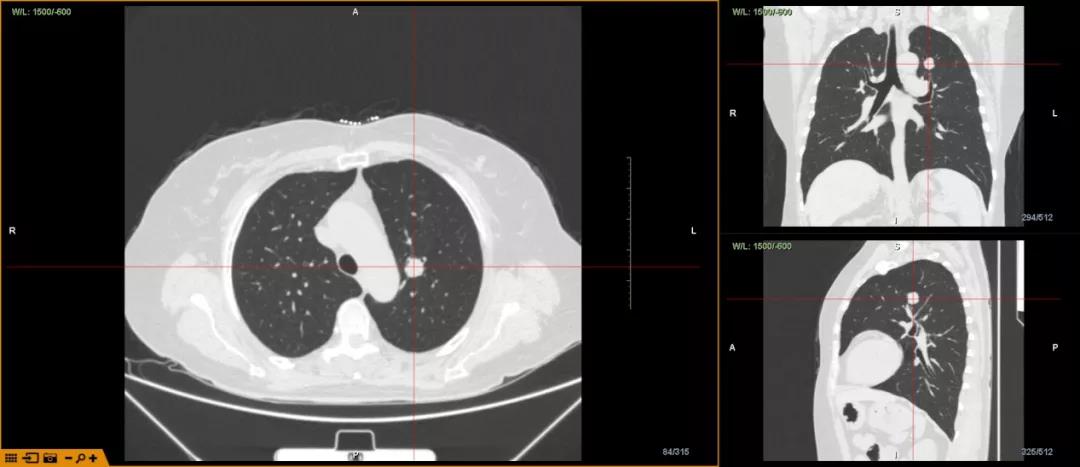

女,54岁,间断胸闷不适半年,伴有灰黑色痰,加重20天CT 提示:左上肺叶实性结节,性质待查。

王晓平主任指出,依据CT影像提示患者病灶在左上叶,病灶临近气道,病灶位置较高,行支气管镜进行活检有一定难度。

将CT数据导入LungPro全肺诊疗导航系统后,系统自动重建全肺血管气管,通过LungPro系统精准识别病灶,明确病灶位于左上叶尖端亚段支开口,病灶临近气道,旁边伴行两根大血管;且明确病灶整体大小,及其与气道、血管的位置关系等后,确定手术方案。